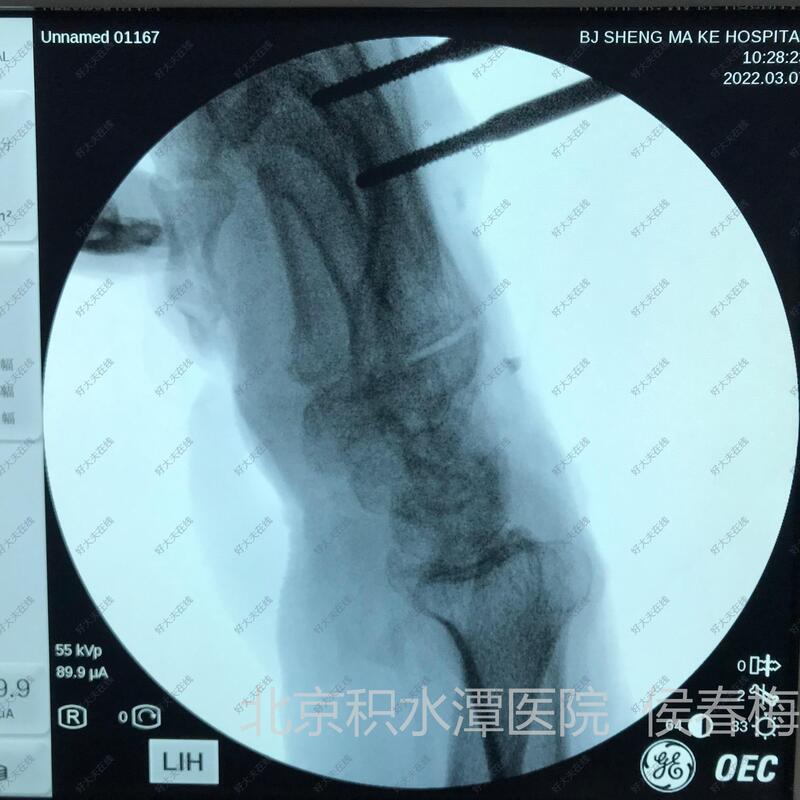

治疗中

手术切除瘢痕,松解伸指肌腱和腕关节背侧关节囊,腹部皮瓣覆盖腕背创面。

腹部皮瓣术后4周,皮瓣血运良好,伤口全部愈合。

早期开始手指屈伸功能锻炼,避免伸指肌腱粘连和关节的僵硬。